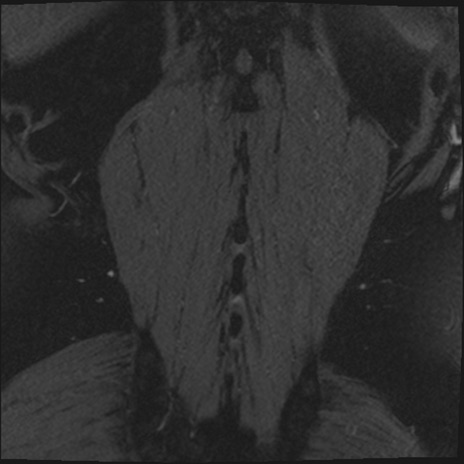

【症例】70歳代男性

【主訴】左下肢痛

【現病歴】2週間前くらいから腰痛、左下肢痛あり。左臀部から大腿、下腿外側のしびれが常時ある。歩行とともに同部位の痛みあり。

【身体所見】Lasegue70-/60+、Bragard-/±、PTR ±/±、ATR -/-、IP 5/5、TA 5/4、TS 5/5、EHL 右第1足趾なし/3、FHL 5/5、hypersthesia(-)、足背動脈触知良好

異常所見と診断は?